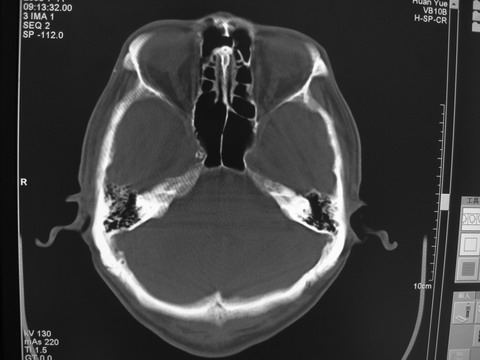

患者 男 69岁 头晕头痛不适

多发病灶,指状水肿,首先诊断转移瘤。

多个结节并周围大面积水肿区,多考虑多发性脑转移瘤

小病灶、大水肿,病灶多发,首先考虑多发转移瘤;建议查原发灶。

额顶叶多发小病灶、大水肿,首先考虑多发转移瘤;建议查原发灶

脑内多发病灶,小病灶,大水肿。

典型转移性肿瘤。

应进一步检查,查找原发病灶。

结果 : 该患者结肠癌病史5年 考虑脑转移